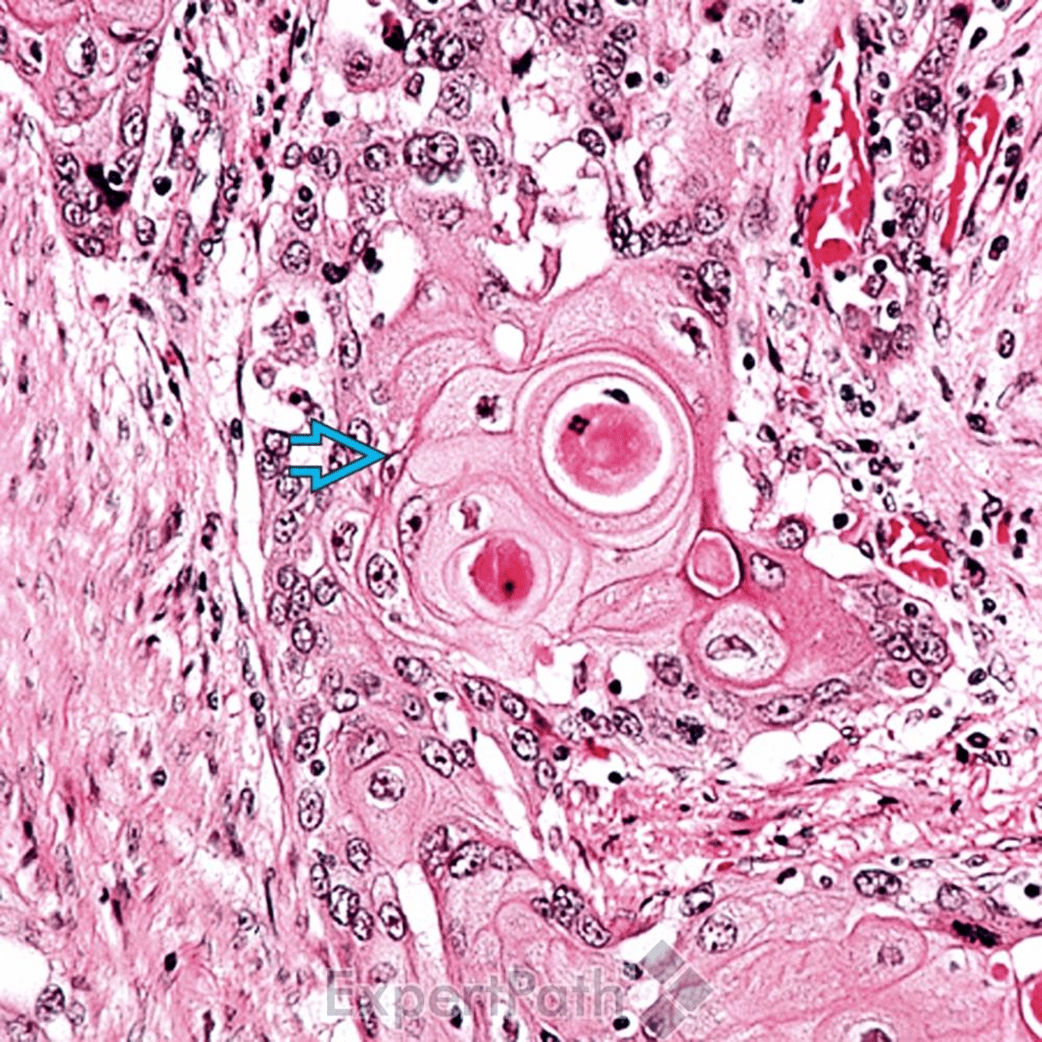

鱗狀上皮癌(Squamous Cell Carcinoma, SCC)

pictures from ExpertPath

Well-differentiated SCC